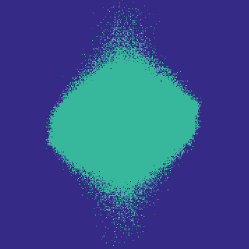

Figure 1 illustrates the best performing randomized indices and our learned set of indices in the plane of the -space. Both the variable density approach [14] and our learning-based approach concentrates its sampling budget on the low frequencies, however the latter is endowed with the capability to adapt its frequency selection to the frequency content of the training signals instead of assuming a circularly symmetric selection.